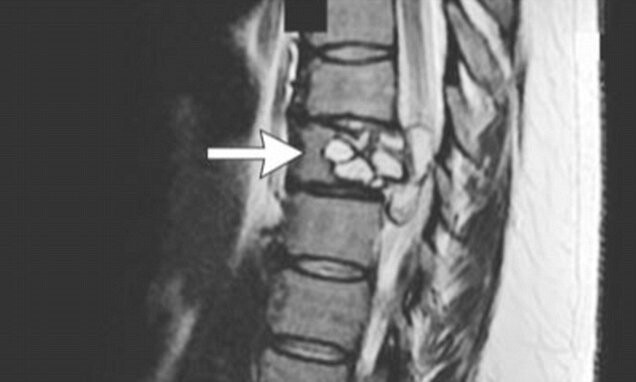

7. Μια γυναίκα στη Γαλλία, η οποία ανέφερε παράξενα συμπτώματα, όπως ηλεκτρικά σοκ να διατρέχουν τα πόδια της, αποδείχθηκε ότι είχε μια σπάνια λοίμωξη από ένα παράσιτο, το Echinococcus granulosous, ένα μικρό σκουλήκι τύπου «ταινίας» που είχε τρυπώσει στη σπονδυλική στήλη της.

Το εν λόγω παράσιτο βρίσκεται σε σκύλους και μερικά ακόμη ζώα κτηνοτροφίας και ίσως έτσι μόλυνε τη γυναίκα, η οποία είχε στο παρελθόν έλθει σε επαφή με άλογα και βοοειδή. Εναλλακτικά, μπορεί να μολύνθηκε, όταν έφαγε κάποια τροφή μολυσμένη με το παράσιτο. Μετά την κατάλληλη θεραπεία, απαλλάχθηκε από τα συμπτώματα μετά από μερικούς μήνες, σύμφωνα με τη σχετική ιατρική δημοσίευση στο περιοδικό «The England Journal of Medicine».